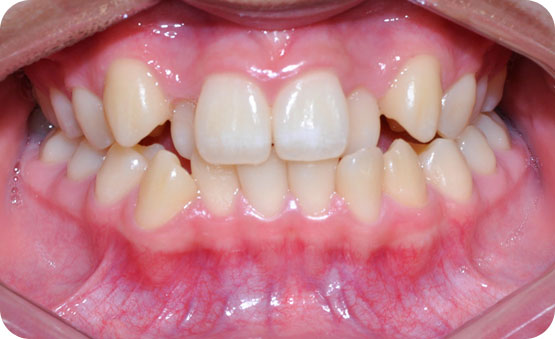

미니스크류를 이용한 하악골 돌출 비발치교정

Before

After